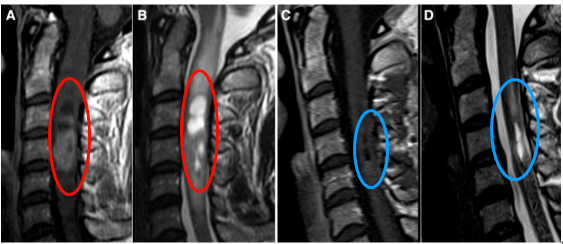

教授在了解到Emma的情况后表示自己可以为其手术。在常规监测体感诱发电位监测下,采取后方入路(Posterior approaches),确定无任何神经损伤的情况下全切肿瘤。

手术成功,术后12天复查,肿瘤全部切除(图C)。且术后水肿几乎完全消失,术前的颈椎疼痛也慢慢消失。术后两周出院,术后一个月她也回归了正常工作与生活。